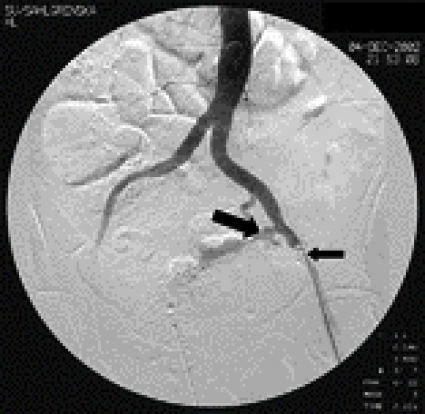

En minimalinvasiv och därmed säkrare metod kan vara att hemodynamiskt stabilisera patienten med en temporärt ockluderande aortaballong (Figur 1) och därefter angiografiskt kartlägga blödningens ursprung med i första hand en översiktlig aortografi. Man vinner härmed värdefull tid och möjlighet att välja mellan de terapeutiska alternativ som finns.

På operationsavdelningen infördes under genomlysning en 30 mm vid ballongkateter perkutant genom en 18 F införingshylsa i vänster arteria femoralis communis. Ballongen expanderades initialt över nivån för avgången för arteria mesenterica superior och retirerades sedan ned mot aortabifurkationen under observation av blödningsintensiteten. Med ballongen expanderad i distala bukaorta stabiliserades patientens tillstånd omedelbart, varefter hon kunde transporteras till en modern angiografiutrustad enhet på röntgenavdelningen.